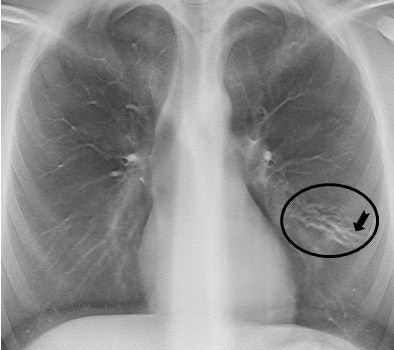

The anteroposterior (AP) chest x-ray, which is automatically included in the examination, shows increased linear markings in the right upper lobe and small parenchymal changes in the left lung, lateral to the heart. All images courtesy of Dr. Kristina Vult von Steyern.

The anteroposterior (AP) chest x-ray, which is automatically included in the examination, shows increased linear markings in the right upper lobe and small parenchymal changes in the left lung, lateral to the heart. All images courtesy of Dr. Kristina Vult von Steyern.In an article published online on 11 November by Insights into Imaging, Dr. Kristina Vult von Steyern, a pediatric radiologist at Skäne University Hospital's Center for Medical Imaging and Physiology in Lund, Sweden, and colleagues described their experiences using digital tomosynthesis imaging with a patient population of 39 adults ages 19 to 59 years and 36 children ages 8 to 18 years. All were participants of a clinical study of cystic fibrosis patients.